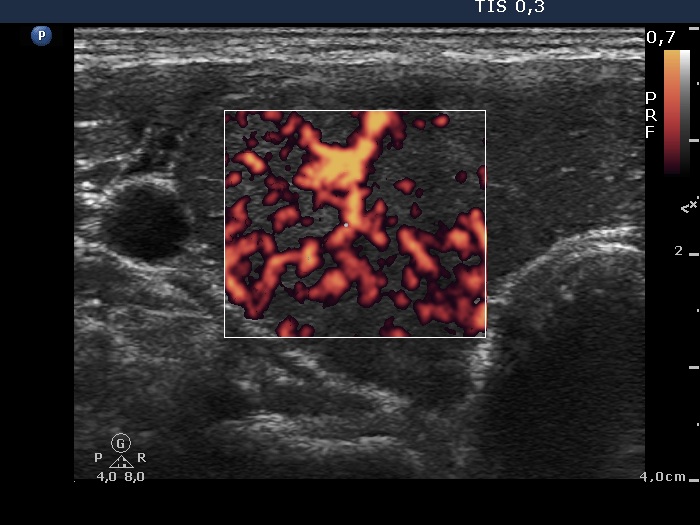

Case 1375 (ultrasonographic picture 4)

Right lobe, longitudinal scan

Right lobe, transverse view, color Doppler mode. The vascularization is increased.